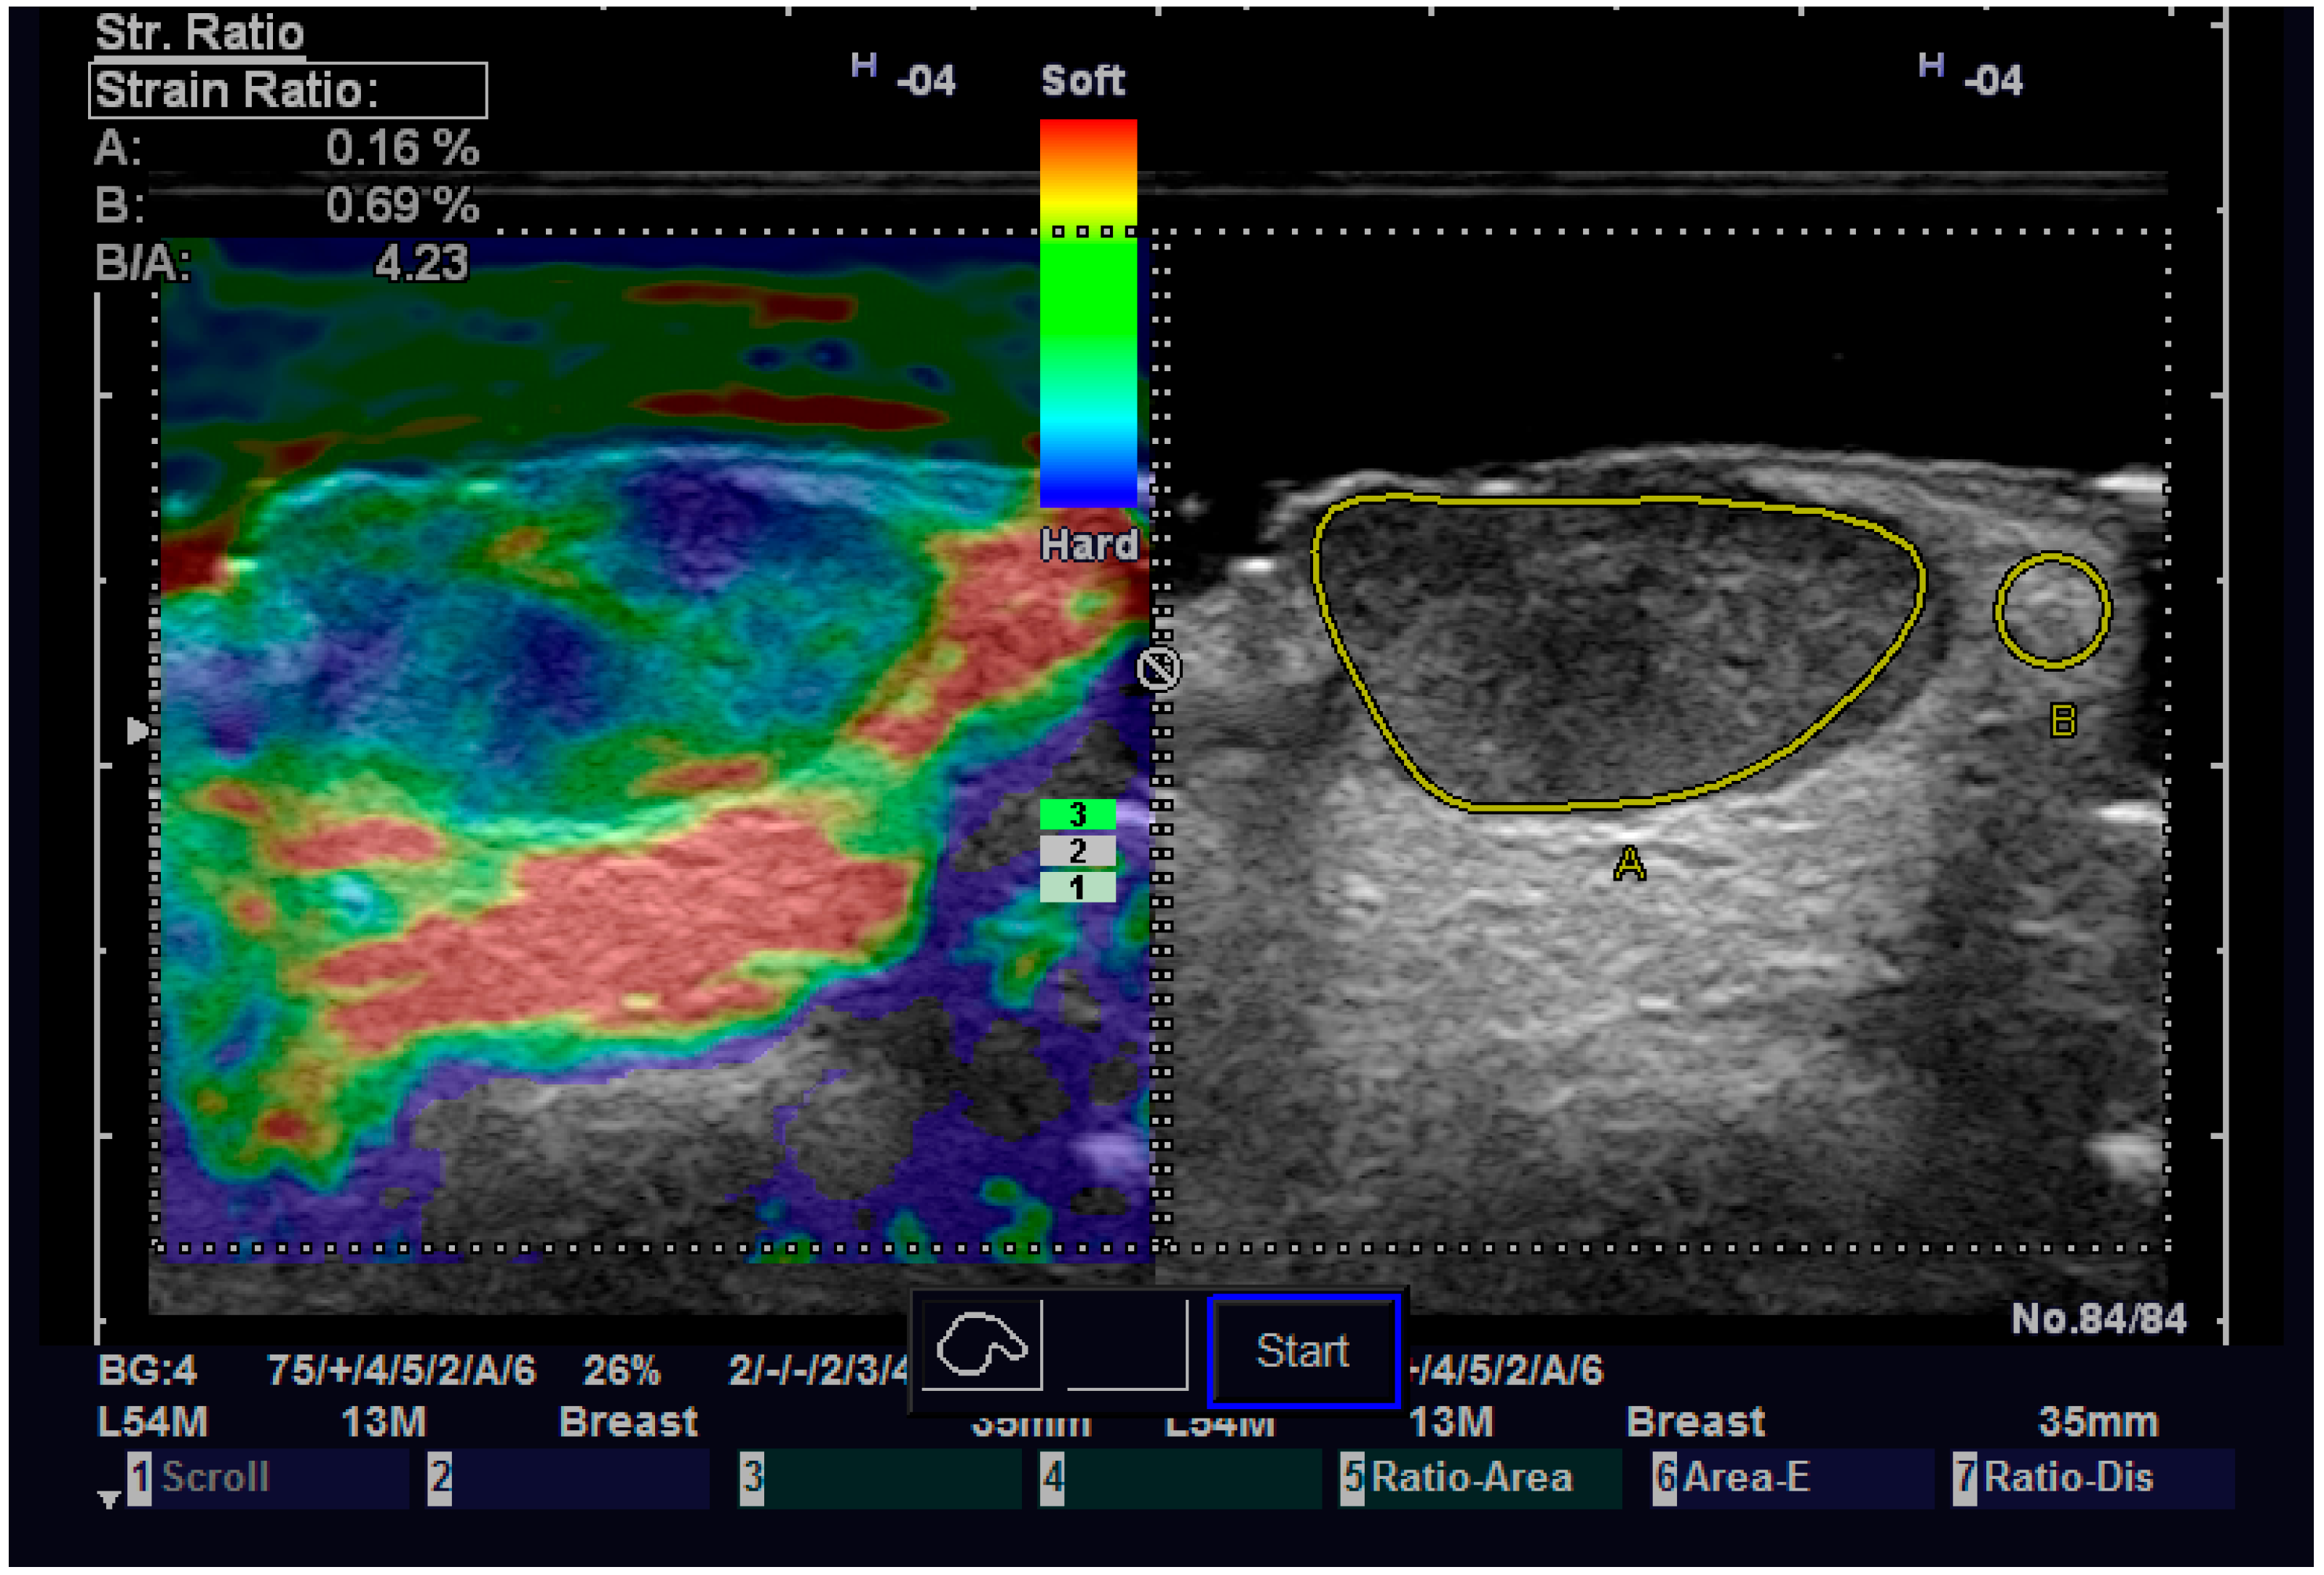

Regarding elastography, we can easily see that the tumor tissue is stiffer than the normal adjacent one (Figure 6). We did not find any significant statistical association between the value of strain ratio and the histology of the tumor. The values in the BCC group were also lower than in the SCC group (95% CI −2.98–0.35, p = 0.126). Doppler examination (Figure 7) showed increased values for both systolic and diastolic speed in the SCC group, but the results were not statistically significant and no association between the type of histology and vascularization was found (Table 4).

Figure 6.

Strain elastography of a SCC.

The strain value in strain elastography serves as a proximate indicator of tissue stiffness or elasticity. Variable skin layers have different elastic qualities, with subcutaneous tissue being more elastic and the epidermis and dermis being less elastic. Increased marginal stiffness is very suggesting for cancer. The malignant tissue develops a fibrotic environment that makes it stiffer than the surrounding tissues [36,37]. Some researchers came to the conclusion that elastography is a variable evaluation that, when combined with B-mode results, may provide the physician or the surgeon with important knowledge regarding different subtypes of BCC. More specifically, infiltrative and non-infiltrative cutaneous basal cell carcinomas are distinguished by enhanced marginal stiffness [38]. Tanaka et al. showed that the tumor thickness of nodular BCC determined by elastography corresponded better with the histological thickness than the tumor thickness measured by traditional B-mode sonography. These results suggest that elastography can be a dependable approach for planning future surgical safety margins since the infiltrative variety of BCC carries a greater risk of recurrence [39]. We did not find any correlation between the nodular or infiltrative type of NMSC and the stiffness of the tumor. We also did not try to measure the thickness of the tumor on elastography, so we cannot confirm the previous result. A certainty that we observed is that the increased stiffness of the tumor compared with the normal adjacent one, which can help us establish the diagnosis of malignant tumor and guide us in surgical treatment.